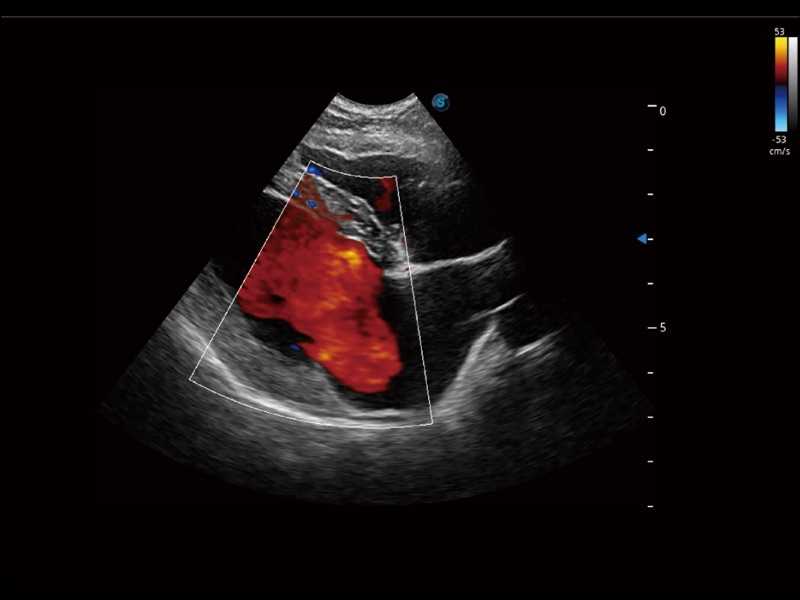

通过创新的 Matrix E自适应滤波器和超长时间域算法,极大提升超低速微细血流的检出能力,同时更精准地滤除软组织和噪声信号,为兽用医生提供以往无法通过常规血流获得的疾病诊断信息。

通过色彩血流和实时宽景相结合,可观察到完整的静脉或动脉的血流,方便医生检查。实时扫查过程中,如有任何操作失误也可以很容易地进行回扫擦除,而不会中断扫查。

采用红、橙、黄、绿、青、蓝、紫这七种肉眼最为敏感的色彩,直观地显示组织内血流灌注的时间先后信息,更精准捕捉血流灌注走行细节。